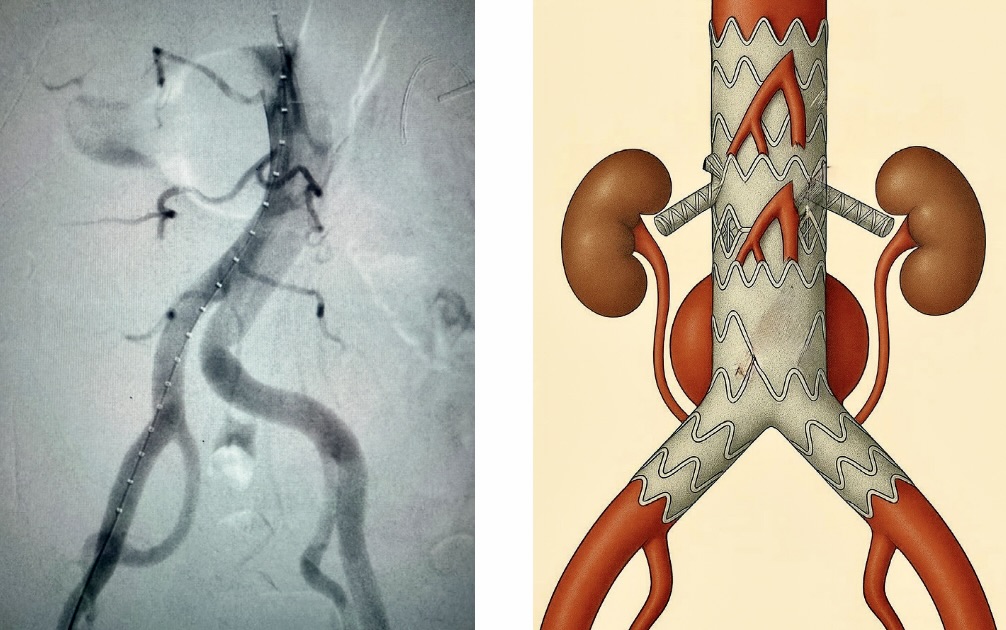

Безусловно, очень важны как мануальные навыки врача, так и его интеллектуальные способности: правильные показания к операции и диагноз на предоперационной подготовке, анализ обстановки и быстрое принятие правильных решений во время операции, умение использовать современные материалы. В сосудистой хирургии появляются все новые и новые материалы: стенты, стент-графты, так называемые эндопротезы, или, к примеру, стенты, содержащие активные компоненты, помогающие разрушать атеросклеротическую бляшку в сосудах и предотвращающие её дальнейшее развитие. Эти современные технологии помогают сосудистой хирургии постоянно развиваться.

Что касается лечения, у сосудистых хирургов есть большой арсенал инструментов, позволяющих лечить как на основе стент-графтов, так и с применением рентген-технологий в рентген-операционных, причем при лечении как срочных, так и хронических состояний - аневризмах грудного отдела аорты или брюшного отдела и смешанных аневризм всех отделов аорты.